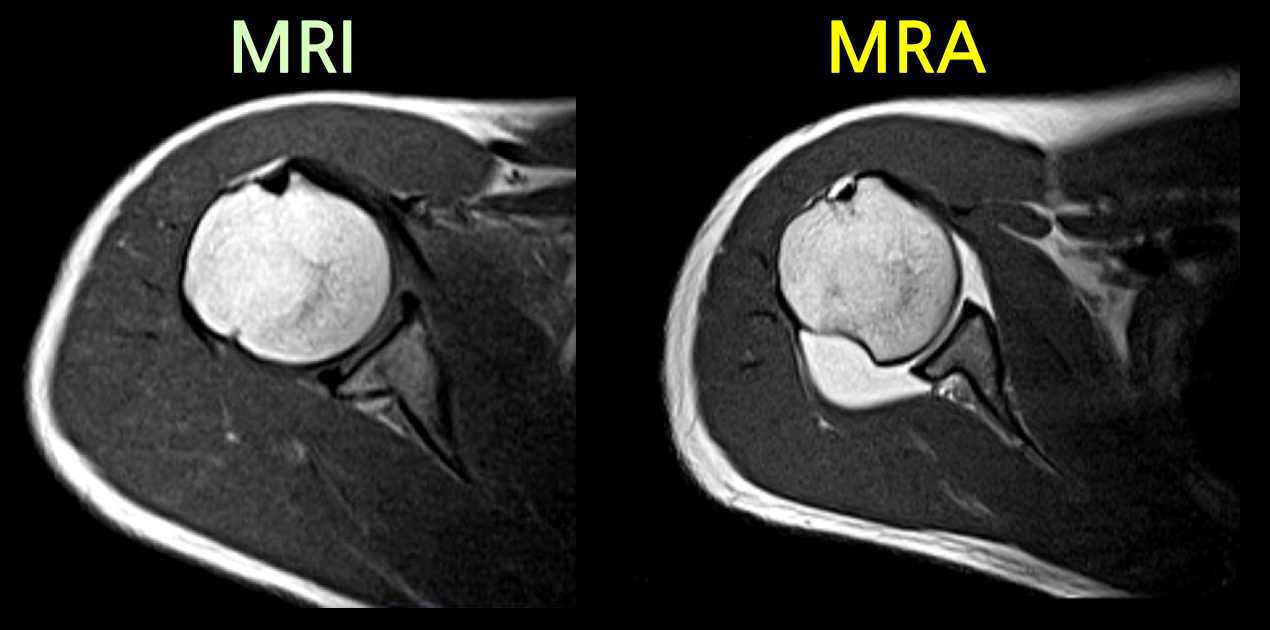

MRA는 MRI와는 다르게 조영제를 사용하며 특히, 같은 부위를 촬영하더라도 조영제 유무에 따라서 촬영된 영상 이미지에 큰 차이가 존재합니다.

작고 좁은 관절에 연부조직을 확인하기 위하여 조영제를 사용하며, 손상여부 및 정도를 확인할 수 있습니다.

정형외과에서 MRA는 어깨, 팔꿈치, 발목과 같은 관절에 적용합니다. 초음파로 확인하기 어려운 관절 전체구조를 확인하고 관절 내 이상소견 및 연부조직 손상여부, 감염등을 확인하는데 큰 도움을 줍니다.

어깨, 팔꿈치, 발목 관절에 조영제를 주입하여 MRI를 촬영하면 조영제가 손상된 틈으로 스며들어 관절 속 미세한 병변까지 진단할 수 있습니다. 이를 관절조영증강 MRI 또는 MRA(Magnetic Resonance Arthrogram)이라고 부릅니다.